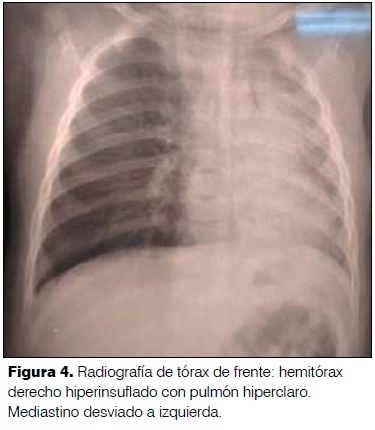

8 meses. Sexo masculino. Medio socioeconómico deficitario. Mal inmunizado. Buen crecimiento y desarrollo. Sano. Comienza 3 días previos a la consulta con fatiga de inicio brusco mientras comía. No episodio de sofocación. Recibe broncodilatadores inhalados con mejoría. Hace 24 horas reinstala fatiga intensa. No fiebre. Al examen: Frecuencia respiratoria 60 rpm. Saturación de O2 ventilando al aire 91%. Aleteo nasal. Tiraje alto y bajo. Quejido. Disminución del murmullo alvéolo vesicular en hemitórax derecho. Estertores secos difusos bilaterales. Hemograma: glóbulos blancos 25.900 elementos/mm3, neutrófilos 55,7%. Proteína C reactiva 11,9 mg/l. Radiografía de tórax: hemitórax derecho hiperinsuflado con pulmón hiperclaro. Mediastino desviado a izquierda (figura 4). Radioscopía con ausencia de cambios con la espiración en hemitórax derecho con atrapamiento aéreo. Mediante broncoscopía rígida se extrae cáscara de lenteja de bronquio fuente derecho. Presenta buena evolución clínica luego del procedimiento.

80,3% de los pacientes presentaron elementos patológicos en la radiografía de tórax, siendo 19,7% normales(10). Los cuerpos extraños orgánicos son radiolúcidos, por lo cual es útil buscar signos indirectos en la radiografía: atelectasia (41%); neumonía (32,4%); atrapamiento aéreo o enfisema obstructivo (23%); desviación mediastinal, neumomediastino, y neumotórax son menos frecuentes(3,12,14). Los elementos radiológicos presentes en esta serie de casos fueron: neumonía, atelectasia, desviación mediastinal, y atrapamiento aéreo.